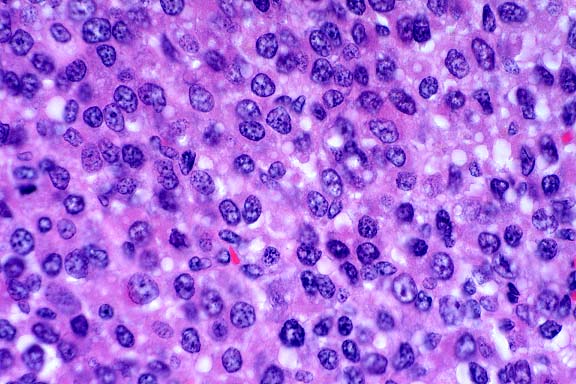

- Contributor's Diagnoses and Comments:

- 1. Testicle: Interstitial cell tumor, with multifocal infarction.

- 2. Testicle: Moderate to severe diffuse atrophy of seminiferous

tubular epithelium, multifocal mineralized intratubular debris

and occasional spermatozoa.

- 3. Omentum: Metastatic interstitial cell tumor.

- Interstitial cell tumors (ICT) are derived from Leydig cells

and rarely metastasize. A continuum was noted from a less well

differentiated cell type which had a hyperchromatic central round

nucleus and a modest amount of a lightly basophilic cytoplasm,

to larger round polyhedral cells with abundant lightly eosinophilic

to vacuolated cytoplasm in the more well differentiated cells.

There was mild cytomorphologic atypia and a slightly higher mitotic

rate (2-4/hpf) in well differentiated areas of the tumor. The

sharply demarcated focus of tumor necrosis is suggestive of vascular

compromise due to possible tumor emboli. Numerous tumor metastases

were noted in the omentum. The mineralized debris in the seminiferous

tubules appeared to obstruct flow, trapping the few spermatozoa

present in the nearby tubules resulting in mild distention.

- Case 16-4. Testis, Epididymis. Replacing seminiferous

tubules and extending around adjacent epididymal tubules, there

is an expansile, infiltrative mass consisting of sheets of polygonal

cells bearing pale granular, often vacuolated cells with oval

to round nuclei with granular basophilic chromatin.

- AFIP Diagnoses:

- 1. Testis: Interstitial cell tumor, malignant, hedgehog,

insectivore.

- 2. Adipose tissue (omentum per contributor): Interstitial

cell tumor, malignant, metastatic.

- Conference Note: A densely cellular neoplasm has effaced

the testis and infiltrated the epididymis. It is composed of

polygonal cells arranged in broad cords, nests, packets and solidly

cellular areas, supported by a fine fibrovascular stroma. In

some areas, neoplastic cells palisade along the vascular stroma.

Neoplastic cells have indistinct cell borders, moderate amounts

of eosinophilic cytoplasm, and oval to elongate nuclei. Some

polygonal cells contain very distinct, clear, cytoplasmic vacuoles.

The mitotic rate is high, and some mitotic figures are bizarre.

Similar neoplastic cells are found within the submitted sections

of mesentery. Based on histomorphology, conference participants

agreed with the contributor's diagnosis. The differential diagnosis

that was considered included seminoma, Sertoli cell tumor, lymphoma,

mast cell tumor, and mesothelioma.